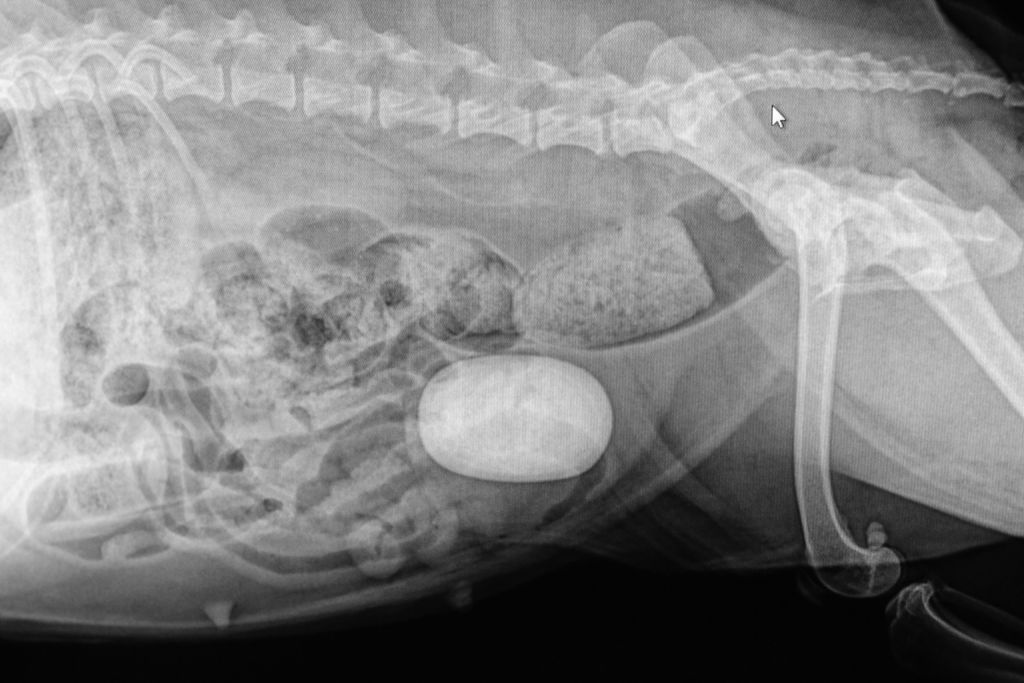

При першій формі зовнішні ознаки хвороби відсутні, і камені або пісок можна виявити, тільки провівши спеціальні дослідження (ультразвук, рентген, аналіз сечі).

Наявність каменів може визначити виключно ветеринар на рентгені